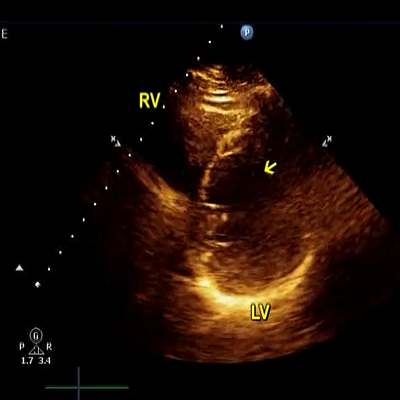

Arrow in point to false tendon

937 KB